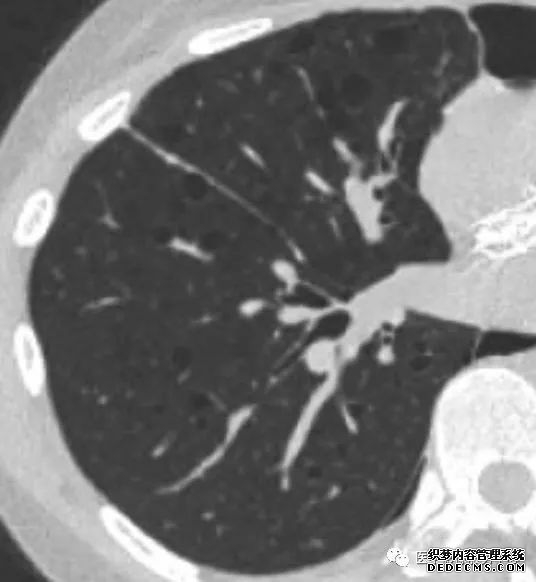

肺转移瘤的十种不典型CT表现